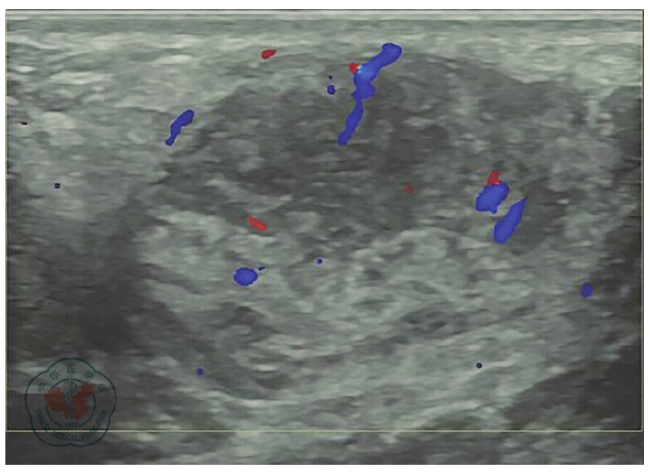

一、临床资料

图2 乳腺及副乳腺假血管瘤样间质增生患者左腋窝彩色超声检查